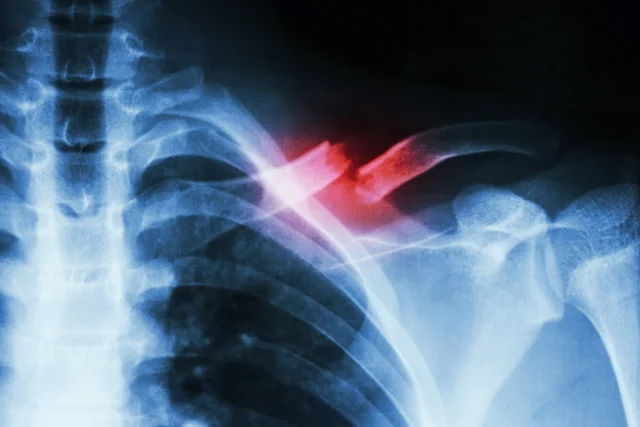

Según fuentes policiales consultadas por Iguazú Ahora, el accidente que ocurrió esta madrugada, el hombre, Sebastián F. de 25 Años de edad que iba conduciendo un Peugeot 405, se encuentra con lesiones graves presentando fractura de de clavícula y fractura tibiaperone, con 40 días de recuperación.